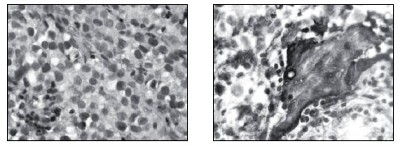

Stereotakticky navigovanou biopsií byl odebrán vzorek tkáně, ve kterém patolog potvrdil maligní germinální nádor typu germinomu se složkou syncitiotrofoblastu obsahující velké polygonální buňky v solidních ložiscích a hnízdech s velkými centrálně uloženými jádry (imunohistochemie: PLAP pozitivní; ostatní, tj. S100, AE1/AE3, LCA, NSE, synaptofyzin, AFP negativní; vysoké Ki67 90 %) (obr. 5 – barvení HE, zvětšeno 400x, obr. 6 – pozitivní průkaz syntitiotrofoblastu při imunohistoche v rámci CNS byla vyloučena. Dítě zahájilo léčbu dle protokolu ACNS 0232: chemoterapie s následnou radioterapií diferencovanou dle léčebné odpovědi, selektivní zvážení tzv. „second look operace“ po 2 a nebo 4 cyklech chemoterapie (3). K blokádě efektu testosteronu na cílových receptorech byl nasazen anti-androgen cyproteron acetát. U pacienta bylo zahájeno genetické šetření vzhledem k sekvenci 2 rozdílných malignit včetně vyšetření na průkaz mutace (dysfunkce) v obvyklých nádorově – supresorových genech či genech DNA reparačních systémů.